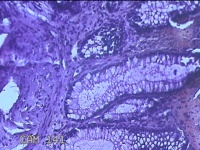

肛门肿物

性别

男

年龄

40岁

临床诊断

混合痔

一般病史

反复肛门肿物突出15年。

标本名称

大体所见

灰白暗红色肿物0.7x0.5x0.2cm一个,表面糜烂。

脱水、透明,浸蜡、脱蜡效果不佳,制片质量差。